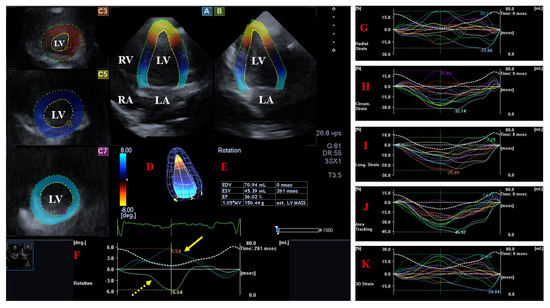

Long-Term Follow-Up of Professional Soccer Players: The Analyses of Left and Right Heart Morphology and Function by Conventional, Three-Dimensional, and Deformation Analyses

Background: Transthoracic echocardiography (TTE) is the primary imaging modality to assess cardiac morphology and function. In athletes, distinguishing physiological adaptations from pathological changes is essential. This study aimed to evaluate long-term cardiac structural and functional changes in professional soccer players. Methods: This retrospective [...] Read more.

Background: Transthoracic echocardiography (TTE) is the primary imaging modality to assess cardiac morphology and function. In athletes, distinguishing physiological adaptations from pathological changes is essential. This study aimed to evaluate long-term cardiac structural and functional changes in professional soccer players. Methods: This retrospective study included 20 healthy male professional soccer players (mean age 21.2 ± 3.4 years) from the German first division, examined annually from 2016 to 2024 (mean follow-up 5.6 ± 2.0 years). TTE parameters associated with the “athlete’s heart” were assessed, including left ventricular end-diastolic diameter (LVEDD), interventricular septal thickness (IVSD), relative wall thickness (RWT), indexed LV mass (LVMi), and left atrial volume index (LAVi), along with 3D-derived LV and RV volumes. Advanced deformation imaging included global longitudinal strain (GLS), right ventricular strain (RVS), and left/right atrial reservoir strain (LASr and RASr, respectively). Baseline and final follow-up values were compared. Results: No significant changes were observed over time in conventional or advanced echocardiographic parameters (e.g., LVEDD: 54.5 ± 3.1 mm vs. 54.6 ± 3.9 mm; p = 0.868; GLS: −18.7% ± 2.2% vs. −18.4% ± 1.9%; p = 0.670). Ventricular volumes and strain values also remained stable throughout follow-up. Conclusions: Over a mean follow-up of more than five years, professional soccer players showed stable cardiac morphology and function without evidence of pathological remodeling. These findings support the concept that long-term high-level training in mixed-discipline sports leads to balanced, physiological cardiac adaptation. Full article